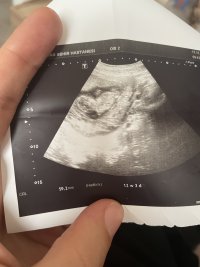

H Hayırlısı Hamiş Melek 18 Kasım 2022 #173 12+3 olduk biz 10+2 de kız demşştiniz fikriniz aynı mı acaba ☺️